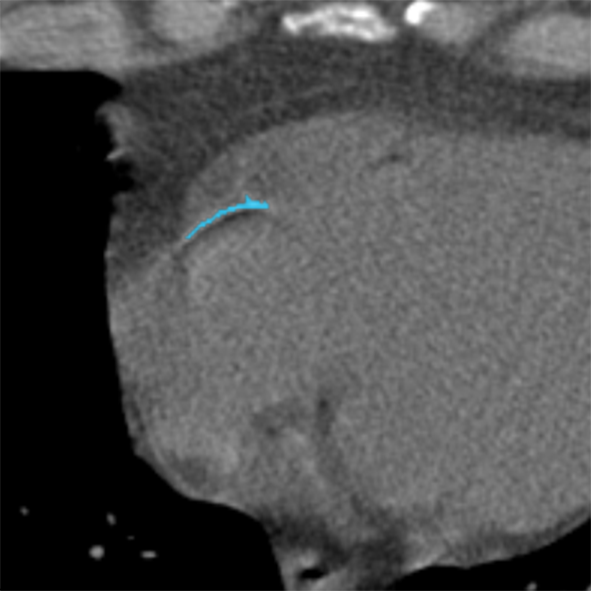

Original image Image with overlay

Calcium scoring is normally performed in images with soft tissue reconstruction. However, lung cancer screening data also includes images reconstructed with sharper filter kernels, in which edges but also noise appear more prominent (Figure 5). To evaluate whether our method needs to be trained with images that are reconstructed with parameters recommended for calcium scoring (soft tissue filter kernels) or whether it can be trained with all images acquired in the screening (see Table I), two pairs of CNN1 and CNN2 were trained: one pair using soft reconstructions only and the other pair using both soft and sharp reconstructions. Furthermore, to evaluate whether calcium detection can be performed in images reconstructed using soft and sharp filter kernels, and to evaluate which of the two training settings leads to best performance, we evaluated our method separately on soft and sharp reconstructions.